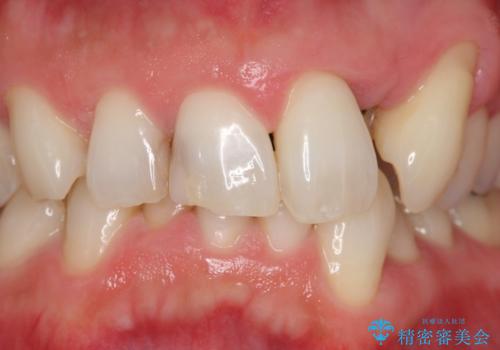

歯並びをきれいにしたい、歯を真っ白にしたい 40代男性

矯正治療とホワイトニングを提案しましたが希望されず、「接客関係の仕事で矯正治療は考えられない、短期間で治療を終わらせたい、ホワイトニングでは難しい位の人工的な白さにしたい」とのご要望により、治療前にワックスアップ模型を作製し何度もコンサルテーションを重ね、治療方針を決定しました。

歯頚ラインが変えられないことや天然歯を削るリスクをご理解頂いた上で、オールセラミッククラウンによる補綴治療を行いました。(見えない奥歯のみ天然歯のままとしました)

クラウンの色味に関して、自然な白さ(シェードA1~NW0.5)のクラウンを作製・試適したところ「もっと白くしたい」と希望され、当院で最も明度の高い色(シェードNW0)に修正しました。

被せ物の種類:オールセラミッククラウン スタンダード (シェード:NW0)